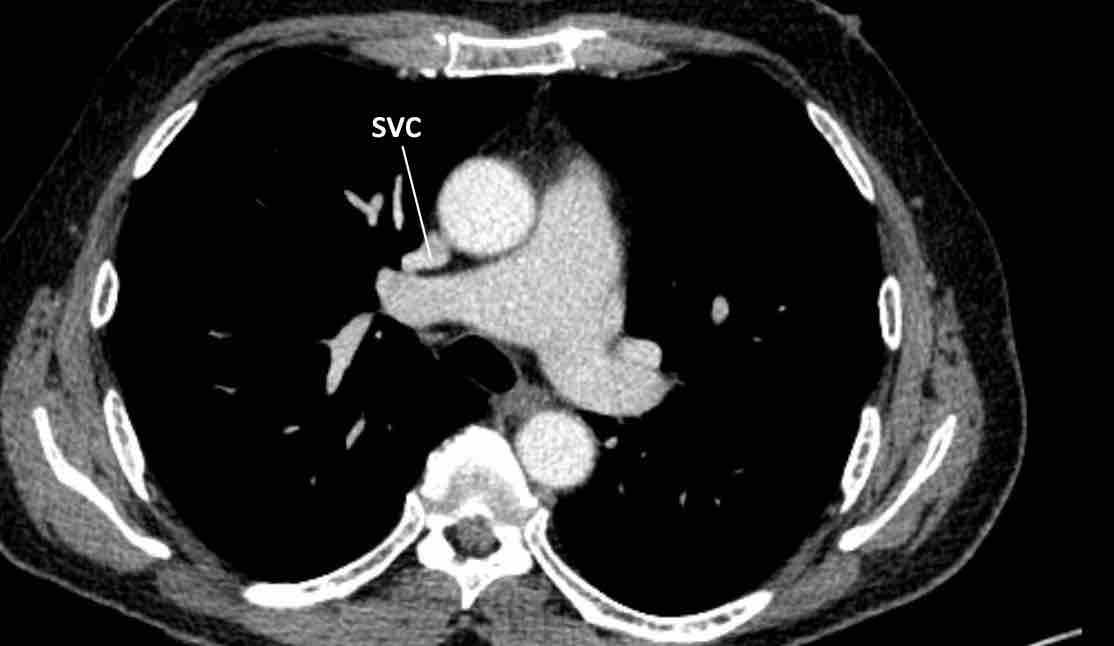

Trong PAPVR, thùy trên trái thường dẫn lưu vào tĩnh mạch tay đầu trái. Bất thường phổ biến tiếp theo là thùy trên phải dẫn lưu vào tĩnh mạch chủ trên.

PAPVR bên phải có mối liên quan chặt chẽ với thông liên nhĩ thể xoang tĩnh mạch (khoảng 40%), đây là một dạng thông liên nhĩ tại vị trí tiếp nối cavo-nhĩ. Do đó, cần kiểm tra sự hiện diện của dạng thông liên nhĩ này khi phát hiện PAPVR bên phải.

Hình ảnh

Bệnh nhân này được lên kế hoạch cắt thùy trên phải do ung thư phổi và bất thường mạch máu này ban đầu đã bị bỏ sót trên hình ảnh CT.

Những hệ quả trong phẫu thuật của bất thường như vậy nhấn mạnh tầm quan trọng của việc không bỏ sót các biến thể này.